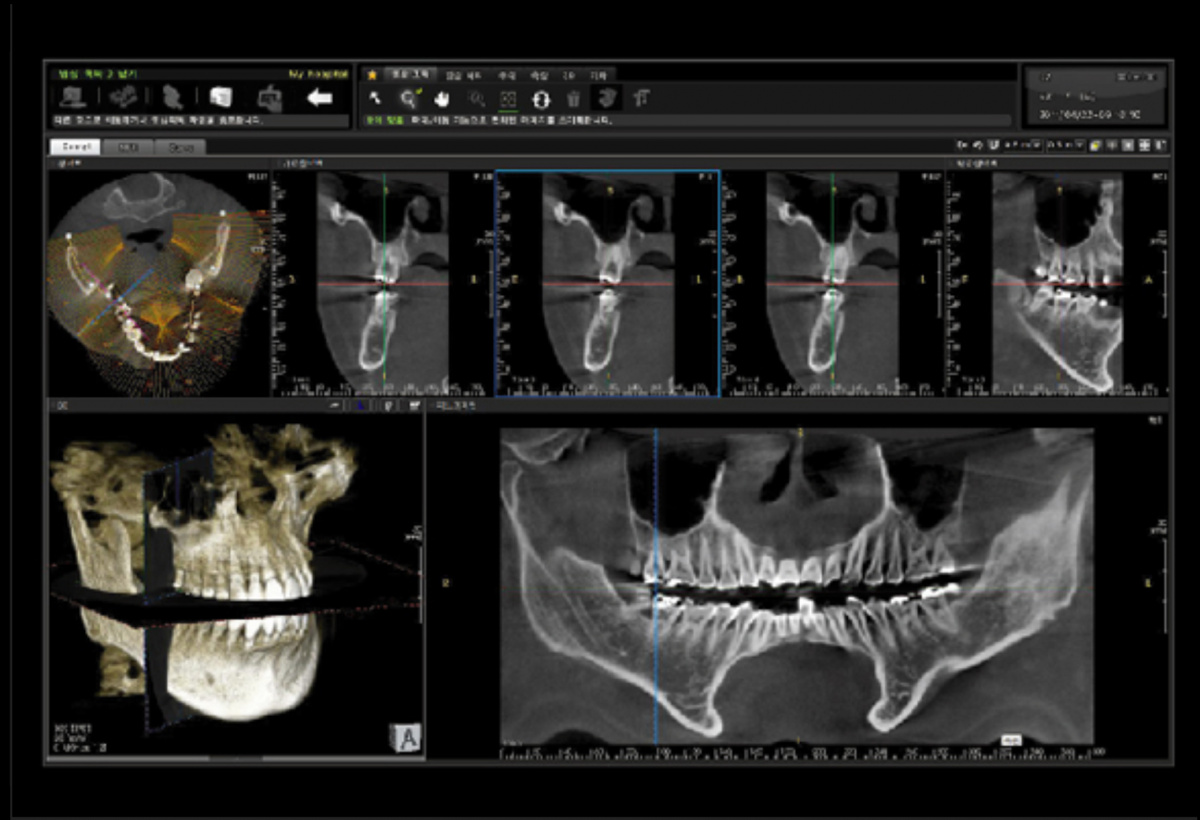

Немаловажным, а может главным вопросом, является универсальность программы-просмотровщика, в которой будут работать врачи-стоматологи. У Papaya 3D есть два варианта программ: Triana и OnDemand3D. Оба просмотровщика обладают схожим интерфейсом и имеют самые важные опции, а именно:

• режим MPR (многоплоскостная реконструкция). Именно здесь выстраивается интересующий участок челюсти или зуба для анализа.

• панорамный реформат. Возможность постройки классической и сегментарной панорамы позволяет продемонстрировать план лечения пациенту, а также оценить расположение анатомических структур на боковых кросс-секциях.

• модуль дентальной имплантации. Возможность виртуальной установки дентального имплантата с анализом окружающей костной ткани. В библиотеке представлен широкий спектр имплантологических систем с индивидуальной прорисовкой имплантата.

• выделение нижнечелюстного канала позволяет продемонстрировать расположение важного анатомического образования и определить зону безопасности при проведении лечения.

• функции плотности, линейных измерений и угла – необходимы для получения полноценной информации для последующего лечения.

• 3D режим – показывает трехмерную модель челюсти с целью определения аномалий, деформация, а также визуализации виртуальных имплантатов.